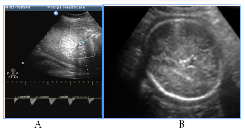

To distress associated antenatal US features of fetal brain could include signs of cortical dysplasia, antenatal intraventricular hemorrhage and PVL (Figure 9) (Figure 10). PVL in the form of small cyst was observed in two fetuses with different premorbid background one fetus with severe prenatal distress and the others with neuroinfection. Particularly attention deserved severe postnatal aftermath of fuzziness and reduced contrast of the fetal brain structures due to cerebral edema and cortical laminar necrosis at 5cases which had different pathogenetic background (Figure 10). Such contrast of structures looked like a result of wrong exposure while getting a picture, but thats were real images, with progression of edema structures looked absolutely "blurred" and cystic PVL lesions were detected. Postnatal catamnesis of all cases was extremely unfavorable.

A number of fetal intracranial changes as cortical dysplasia, intraventricular hemorrhage, PVL and reduced contrast of the fetal brain structures were observed both in infection and in severe placental dysfunction. Most of such anomalies had periventricular or subependymal localization, which could associated with universal polyetiologic pathogenetic mechanism of the germinal matrix injury. Figure 9 Antenatal distress associated sonographic brain features. A) Revers diastolic flow in the umbilical artery. B). fuzziness and reduced contrast of the fetal brain structures due to cerebral edema on the background of antenatal distress and metabolic acidosis. In clinical catamnesis perinatal loss and extremely severe persistent neurologic morbidity.

Figure 10 Fetal distress associated small-cystic PVL in the fetus and newborn. A) 31 GW, severe IGR, fetal metabolic acidosis, fuzziness and reduced contrast of the brain structures due to cerebral edema, skull deformation due to cortical necrosis, small cysts PVL in the intermediate zone (arrow). B) NSG of the newborn's brain of on the 2nd day of life, progressive small-cystic PVL. Neonatal death.